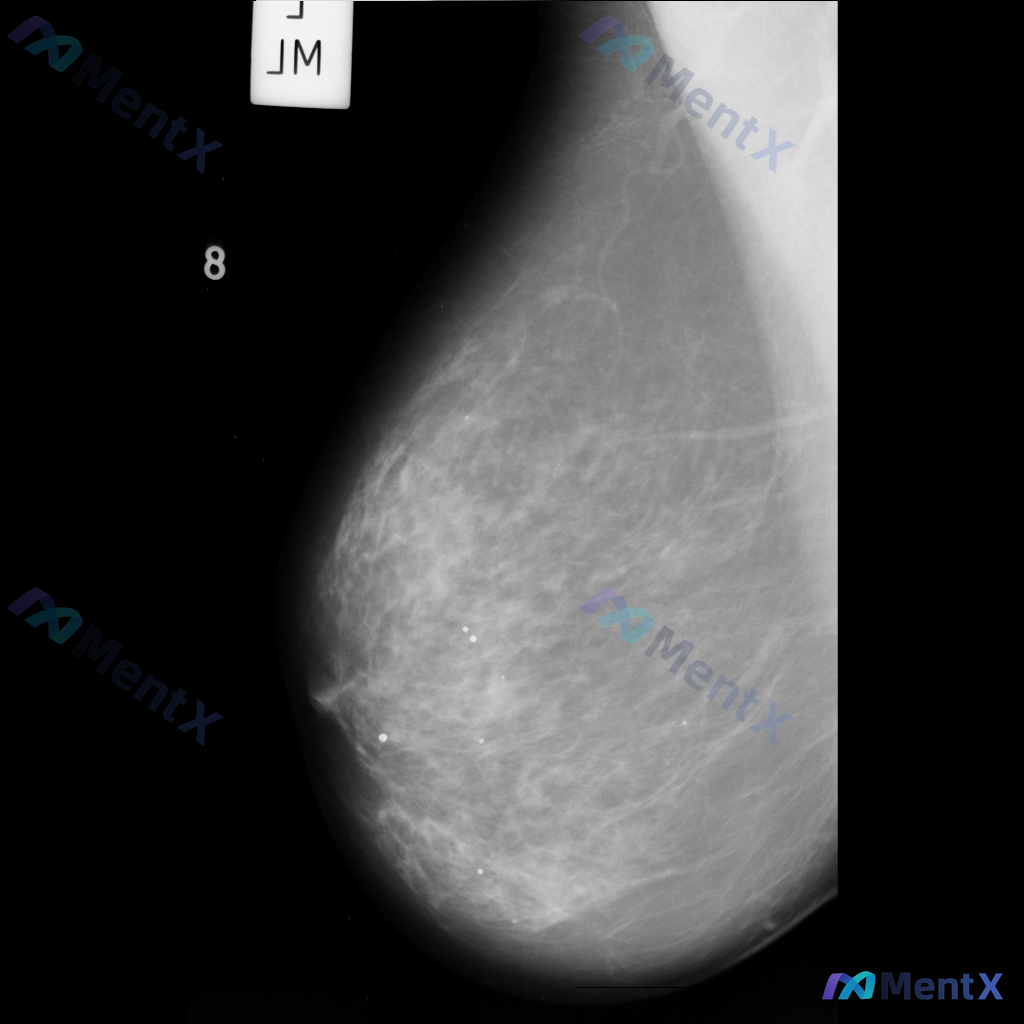

各位老师好,这里有一张乳腺钼靶影像(image: mdb281.png),影像中可见一些异常表现,想请大家一起讨论一下。

整理到一张单侧乳腺钼靶影像的读片资料,目前是单一体位图像,没有双侧对比。 影像表现整理 - 乳腺组织密度较高,属于多量腺体型或致密型背景 - 可见散在的钙化灶:图像中部偏下有数个点状或粗大钙化,形态不规则,但无典型恶性钙化的细小多形性、线样或分支状表现 - 乳腺下象限可见多个高密度圆形/卵圆形影,边...

整理了一份乳腺影像的读片资料,想和大家讨论下判断方向: 基本影像信息 - 单侧乳腺X光片,投照体位考虑可能为内外斜位(MLO) - 乳腺组织构成:不均匀致密型 - 影像质量:曝光适中,清晰度良好,无明显伪影 - 可见结构:皮肤、皮下脂肪层、乳头乳晕、Cooper韧带显示尚可;未见明确钙化血管或腋窝淋...

整理到一张左乳内外斜位(MLO)的钼靶影像资料,先和大家讨论一下读片的情况。 目前已知的信息: - 仅提供了左乳的MLO位单张投照影像 - 影像质量基本良好,基本结构可辨 - 后续补充说明提到患者的乳腺构成类型为不均匀致密型(BI-RADS C) 目前暂时没有更多临床病史、对侧乳腺影像或头足位(CC...